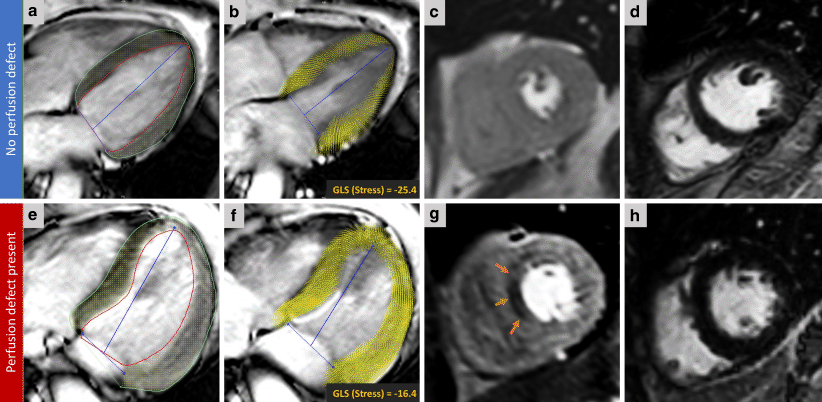

Fig. 2

Two case examples: Case 1 (a–d). The top row shows CMR images of a 63-year-old female who presented with a history of chest pain. Panel a illustrates endo/epi contours on 4‑chamber cine acquisition at peak stress. Panel b demonstrates the derived myocardial feature tracking and computed systolic GLS at peak stress. Panel c shows the corresponding stress perfusion image at the time of peak myocardial contrast enhancement, showing no inducible perfusion defects. Panel d shows that there is no infarction on late gadolinium enhancement (LGE) imaging. Case 2 (e–h). The bottom row shows CMR images of a 59-year-old male who presented with a history of chest pain. This is a case with a perfusion defect in mid-ventricular septum (orange arrows in panel g) on first-pass perfusion with no evidence of previous myocardial infarction on LGE imaging (Panel h). Notably, the peak stress GLS was significantly lower in this case. (CMR cardiovascular magnetic resonance, GLS global longitudinal strain)

All cine images were of adequate quality for FT analysis. Fig. 2 demonstrates two cases from the study. Rest GLS, GLSR, E’ and stress GLS were significantly lower in the group with a perfusion defect compared with the no perfusion defect group (Tab. 1). Notably, rest GLS was not significantly different in patients without previous myocardial infarction and with/without ischaemia (Tab. 2; Fig. 3).